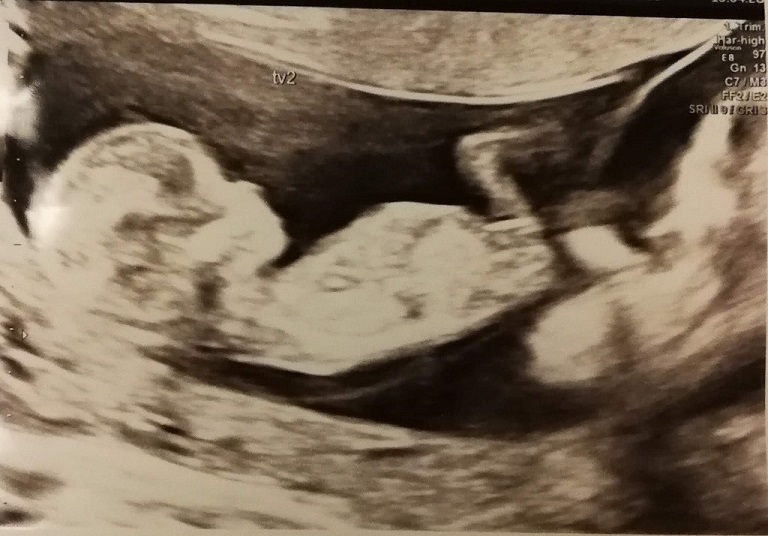

Anybody want to make some nub guesses? :) 12+5 with identical twins. Is it too early? Would love to hear your guesses :)

No clues in the first pic but all girl in the second. Congrats!!:happy:

Second pic looks girly.

cant see a nub in the first one but the second does indeed look girly :P congratulations!!! xo

Second pic looks like a girl